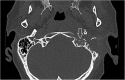

Background: Central skull-base osteomyelitis (CSBO) represents a life-threatening complication of external ear canal infection. Computed tomography (CT) and magnetic resonance imaging (MRI) play key roles in assessment of CSBO progression.

Methods: Twelve patients with CSBO were included in a retrospective clinical study. In total, 62 scans (30 CTs and 32 MRIs) were performed to evaluate the extent of inflammatory changes. The scans were read independently by two radiologists specialised in imaging of the head and neck. The regions under the skull base were specified using the online Anatomy Atlas of the skull base. To clarify the timeline, the time period was divided into four parts, and inflammatory changes in the skull-base regions were tracked. Data were statistically analysed.

Results: In early stages of the disease, CT scan detects inflammatory changes closely related to the stylomastoid foramen and medially to the posterior belly of the digastric muscle, changes which have been proved to be crucial for the diagnosis of CSBO. Later the infection spreads to the contralateral side causing demineralisation of the bones.